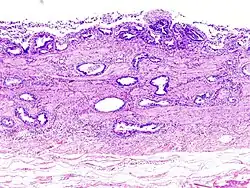

Incidentally discovered gallbladder cancer (adenocarcinoma) following a cholecystectomy. -

Gallbladder adenocarcinoma histopathology -